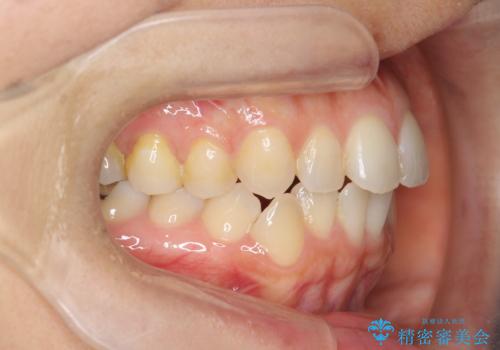

前歯のがたつきをしっかり治すマウスピース矯正

- 前歯のガタガタをきれいに並べたい、と希望され来院されました。

マウスピース矯正インビザラインのクリンチェックを用いて治療前にしっかりと歯並びのゴールのシミュレーションを行い、治療を開始します。

がたつきのないきれいな歯並びに仕上げることができ、満足いただくことができました。